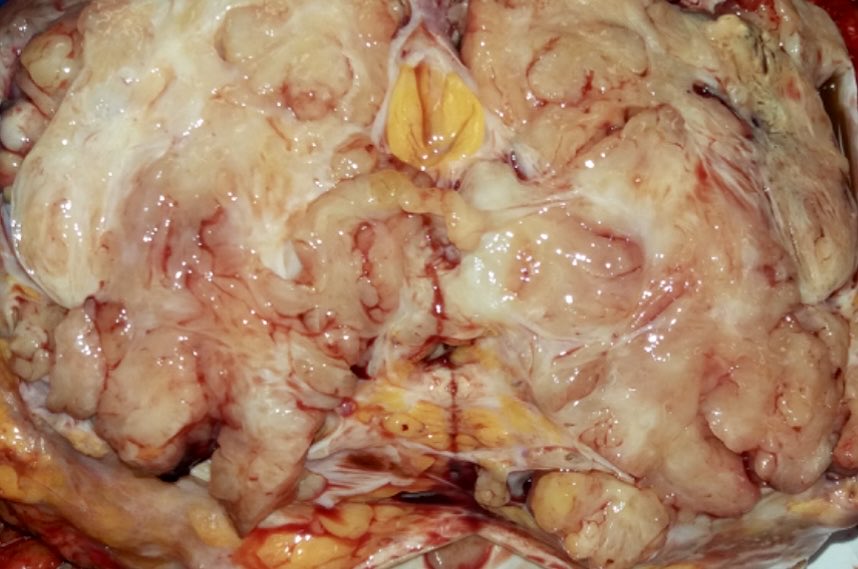

The art of grossing. A 3 year old boy presented with abdominal mass and hypertension.Total Right Nephectomy performed.Two lesions were found, a 3.5x3cm prominent cystic tumor and a 4.2x3cm solid and round mass. Final Dx.Wilms Tumor.#pathology #pathres #GUpath

vintage81106614's tweet image. The art of grossing. A 3 year old boy presented with abdominal mass and hypertension.Total Right Nephectomy performed.Two lesions were found, a 3.5x3cm prominent cystic tumor and a 4.2x3cm solid and round mass. Final Dx.Wilms Tumor.#pathology #pathres #GUpath